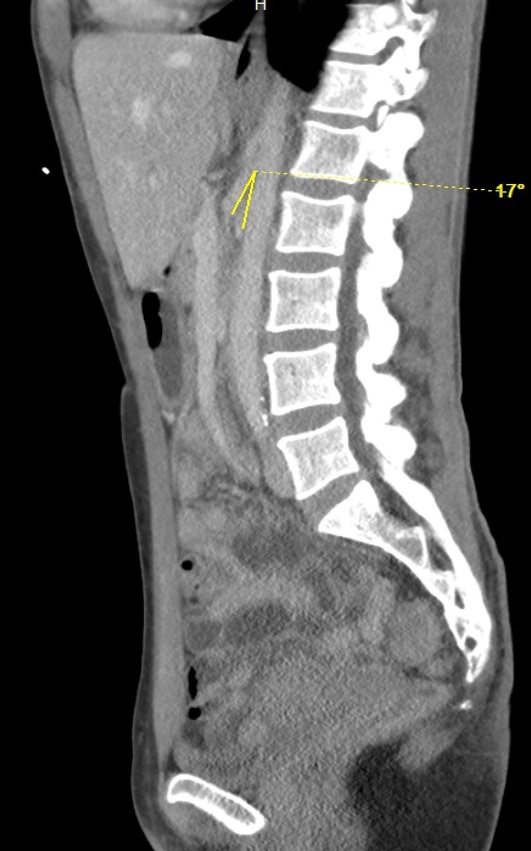

Introduction: Wilkie's Syndrome, also known as Superior Mesenteric Artery Syndrome (SMAS), is a rare cause of bowel obstruction that can contribute to vague abdominal symptoms on clinical presentation. This syndrome occurs when the aortomesenteric angle decreases, compressing the third portion of the duodenum between the aorta and the superior mesenteric artery. An acute decrease in the mesenteric fat pad cushion between these two blood vessels is the primary etiology, although other causes (e.g., anatomical, postoperative, functional, and pubescent etiologies) have also been described.

Case presentation: In the present cases, 2 females with a common history of recent weight loss presented to our institution with similar symptoms of abdominal pain, nausea and vomiting. Each patient was subsequently diagnosed with SMAS following imaging studies. Both patients experienced successful resolution of symptoms with conservative nutritional management.